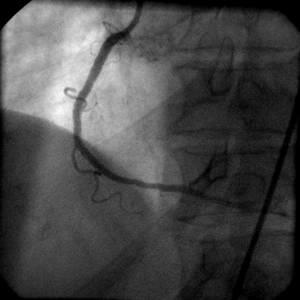

>○○先生; ところで、このIVUSのLowの物って動いていましたか?時期的には

Black holeよりはやはり血栓が考えやすいと思うのですが、血栓にしては形態がどうか

なっと悩んでしまいますステント内血栓ってもう少しもやもやしてるよな印象があるの

ですけど・・・ちなみにこの病変に対しては何か治療されましたでしょうか?

最終的にはこの症例がどうなったかというと、本当はfilter wireやocclusion balloon

を入れて血栓かどうか確認したかったのですが、術者は残りのLCXをやるのにあせって

いてできずステントをいれられてしまいました。ステント留置後のIVUSも添付します

が、こぶはなくなってました。

”なまこ”も”Black Hole"も慢性期にできるものと個人的にはり理解してます。特に

○○先生のIVUSの本のP68にのっているBlack Holeの写真にそっくりですし、、、。し

かし3日で完成してますし、ステント留置で完全になくなってます。またよく見ると5つ

のコブはステントストラットの上にきれいに乗っているような気がしてなりません。個

人的には血栓と考えたいところです。みなさんはどおお考えでしょうか?IVUS上の所見

はecho lucentで似てますのでもしかしたら、構成成分で類似したのもあったのかもし

れません。ステントで末梢に流れてしまったとおもわれますが、病理がないので非常に

残念です。

で。実際の症例では最初アンギオをみていただいてもお解かりだとおもいますが、すご

くFocalで血管径もそれほどではないので、全部血栓だとしても、普段絶対Distal

実際はCypher3.5/8mm/20atmをいれても全然フローは保たれてましたし、小さな枝の抹

消塞栓もみられませんでした。最初のIVUSイメージで11時にあるコブがIVUSのプローブ

がはいったためか上半分がかけているように見えます。NIHではこんなことはおこらな

いでしょうから、おそらく非常にやわらかいけど可動性がないレベルの硬さではないか